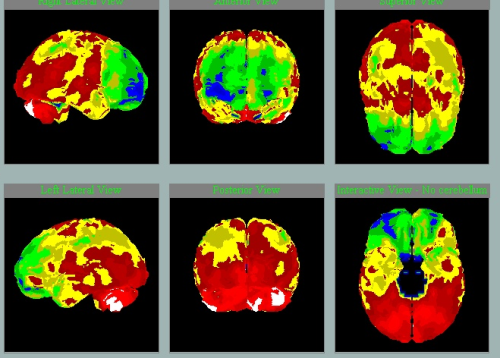

SPECT mozku u pacientky a její dcery

dcera, 54 let, VŠ

matka, 82 let

Hledejte ne 5 rozdílů, ale v čem se oba mozky podobají….